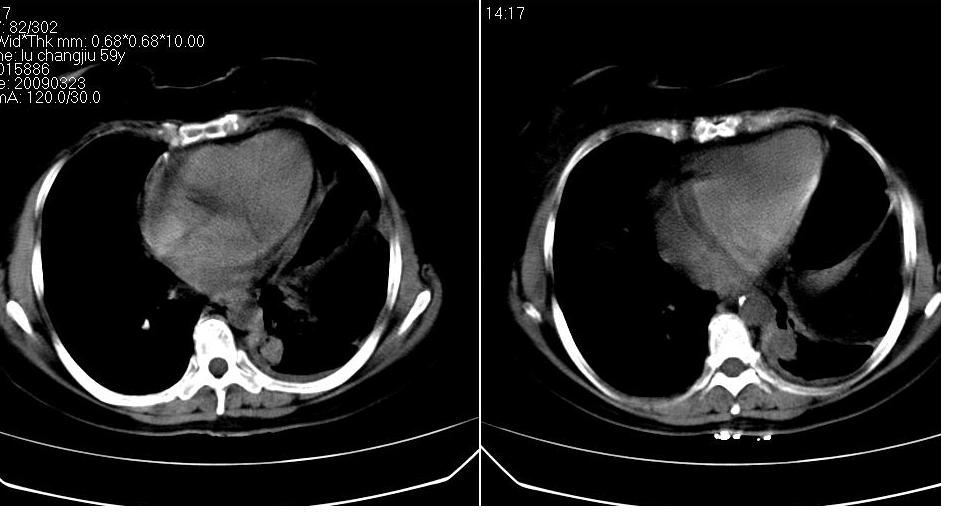

女 59岁,胸背疼,不咳嗽,不咳痰,不发热。

1)考虑左肺下叶背段周围型肺癌并左肺下叶及左侧胸膜转移。2)左侧胸腔积液。3)左冠状动脉钙化。

支持楼上,左侧膈肌抬高,考虑膈疝或膈麻癖可能。

1)考虑左肺下叶背段周围型肺癌并左肺下叶及左侧胸膜转移。2)左侧胸腔积液。